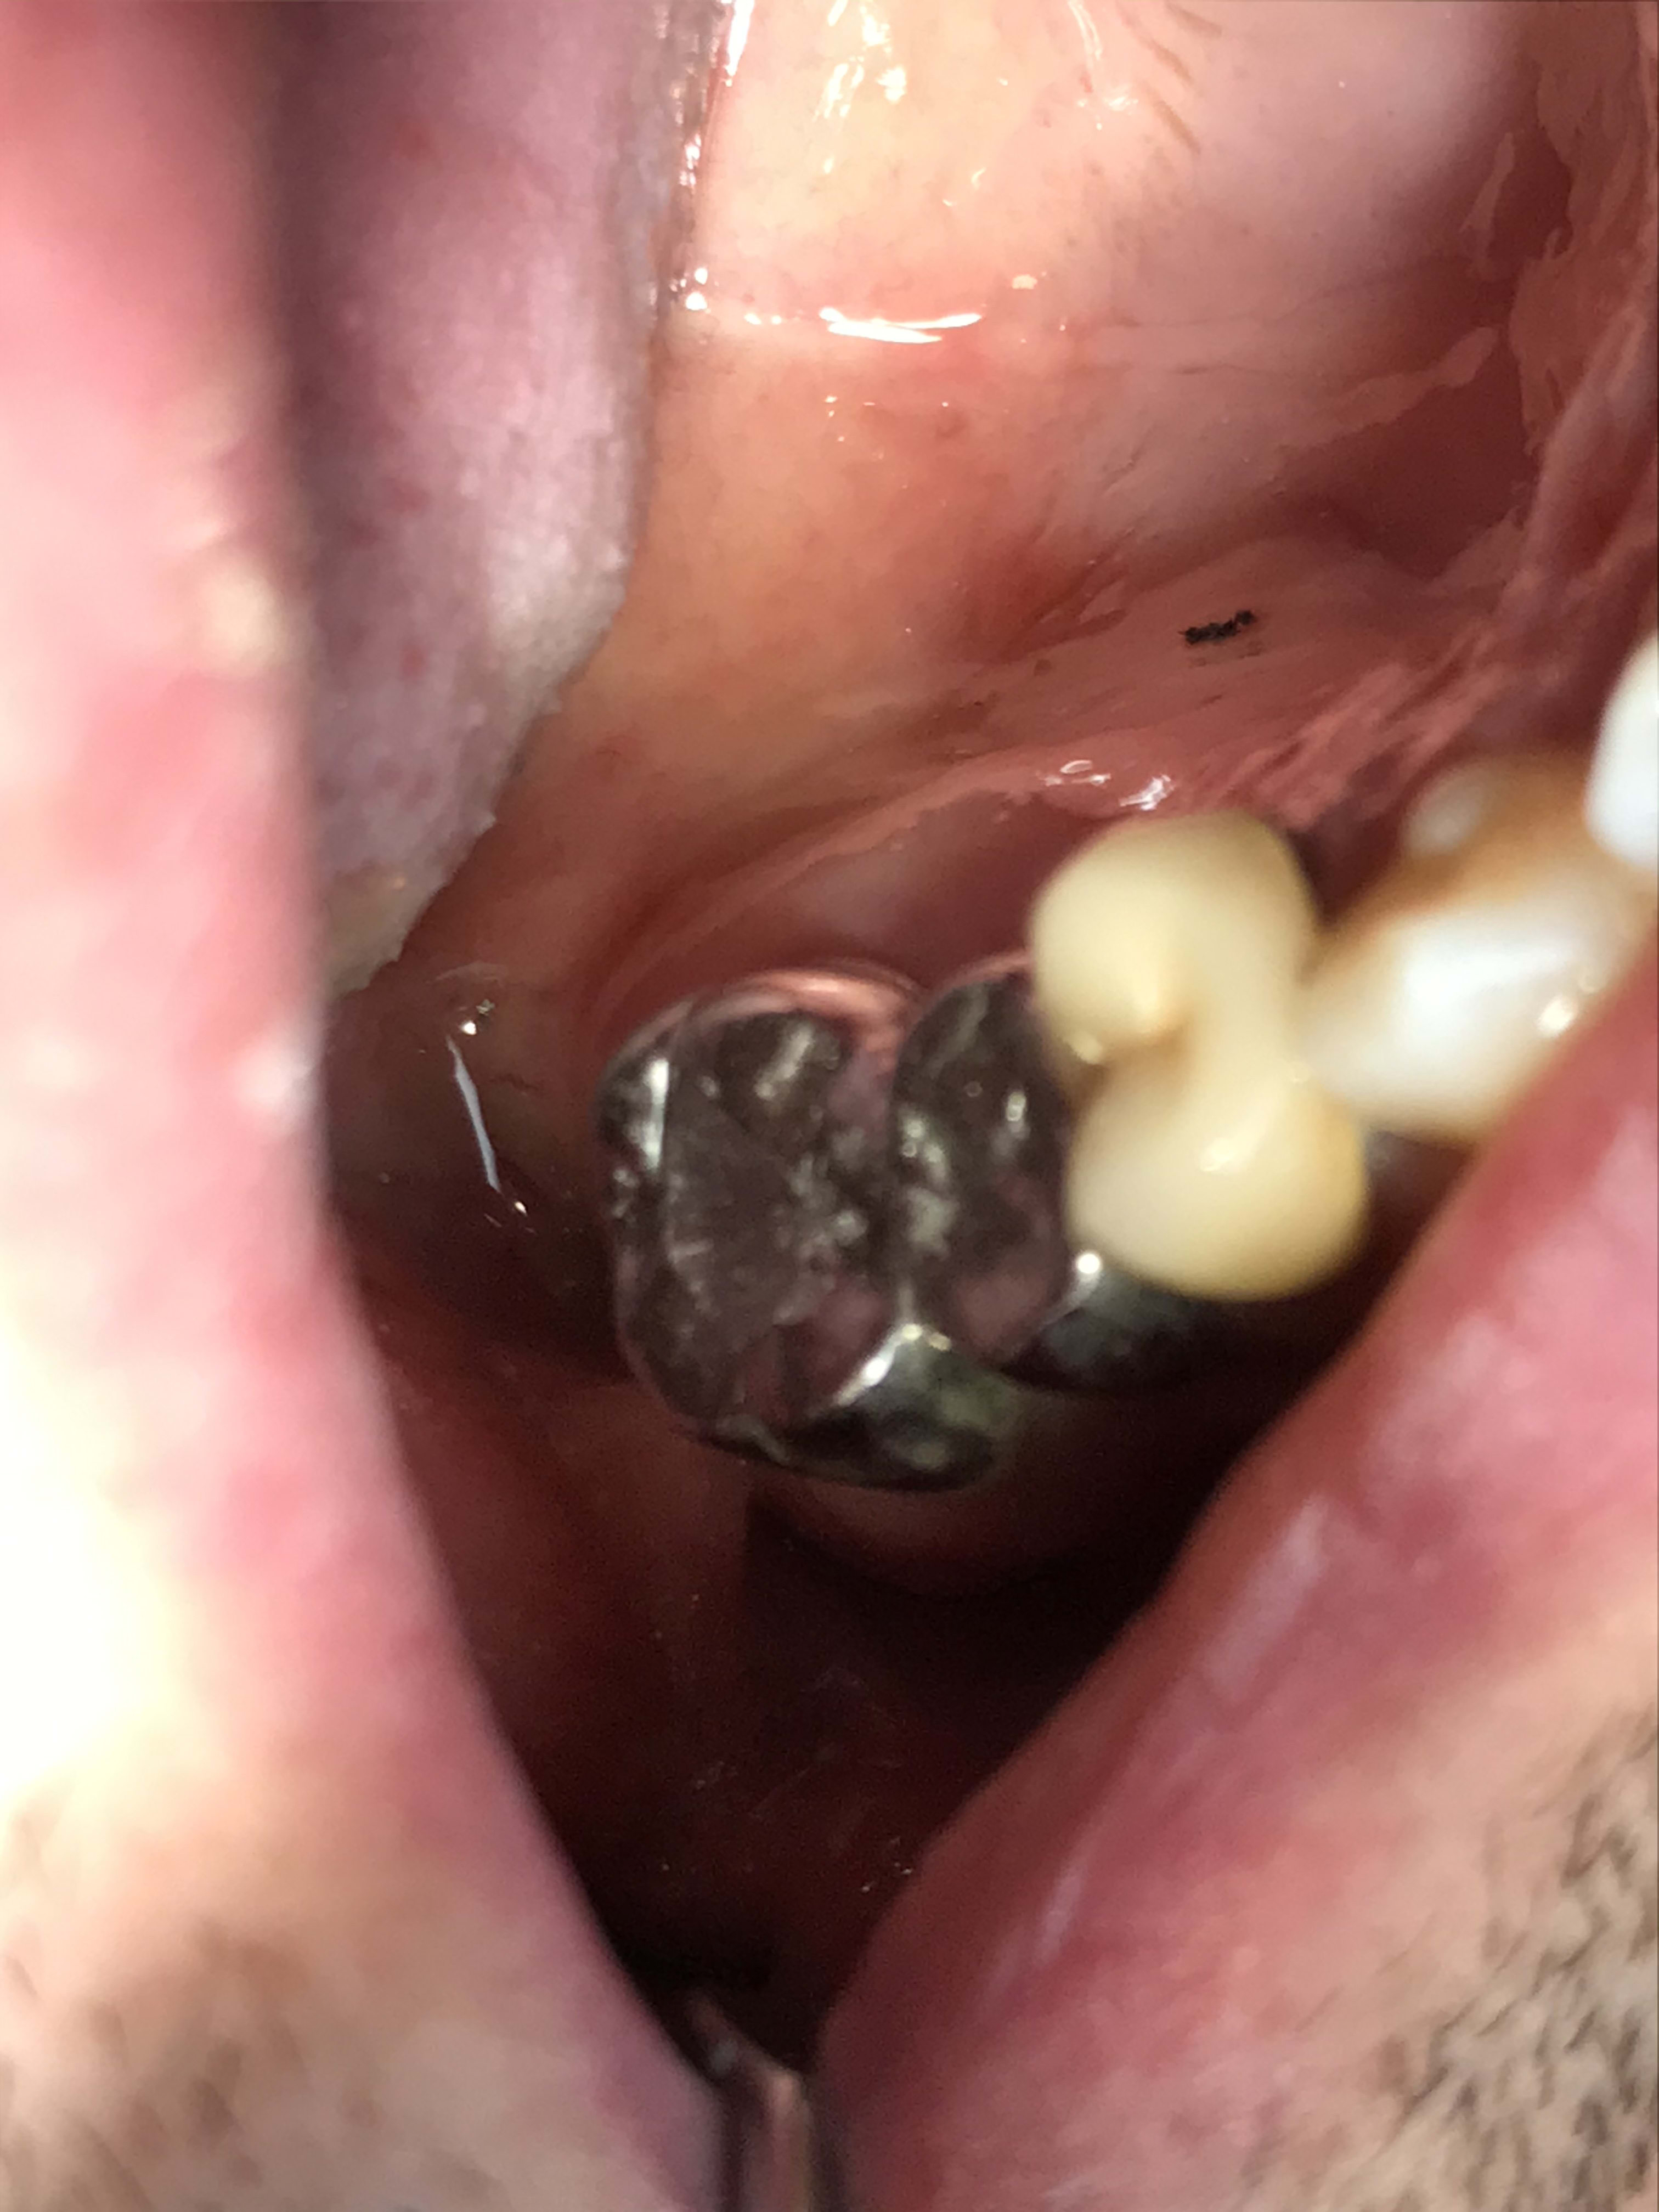

Parce que le composite tient bien dans le temps , une facette en composite avec retour palatin a été faite sur 21. Je récupère la patiente et je note la Durabilité ainsi que l’esthétisme du composite +++. Ça tient bien dans le temps.

Ouais, il a raison Junior, le composite c'est rien que de la merde, ça rend aucun service, ça vieillit super mal...de la daube quoi!

En plus sur le cas avec les diadèmes, y'a pas eu de digue....un travail de gros porc quoi!